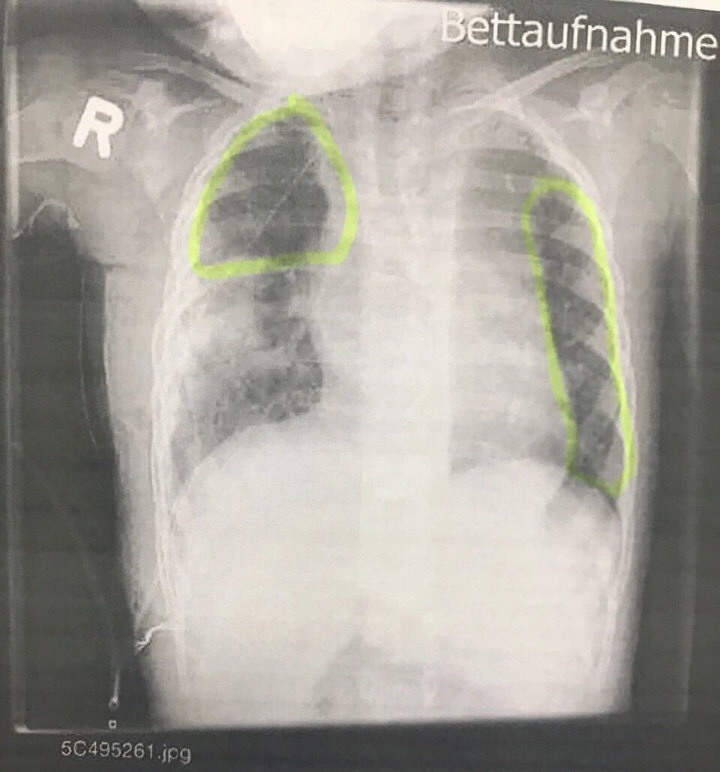

— С Эль-Али Салу Мажди Али я познакомилась случайно в 2007 году, он ливанец, получил российское гражданство. У нас ребенок инвалид детства, дочка перенесла четыре операции. Верхняя и средняя доли правого легкого удалены. Гипоплазия левого легкого (нераскрывшееся легкое), бронхи сужены. Половина кишечника удалена. Ребенок родился с патологией. Операция была сделала в Германии 1 августа 2017 года. Это единственная клиника, которая взялась оперировать моего ребенка.